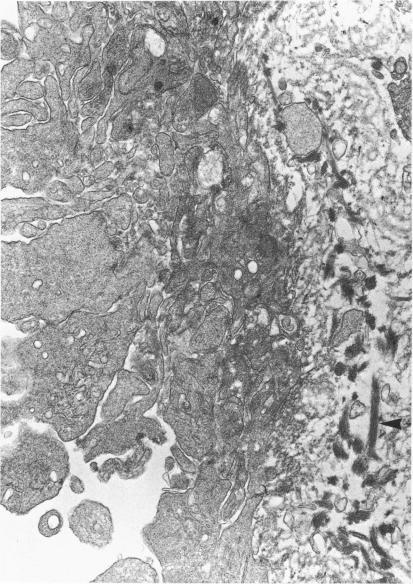

Rabbit arteries, de-endothelialized with an intravascular balloon catheter and allowed to heal for 4 weeks, showed intimal changes that were similar to the preatherosclerotic fibromusculoelastic plaques of man. Reinjury of the healed vessels by balloon catheter produced marked quantitative and qualitative alterations of hemostasis, as compared to that in previously uninjured vessels. The most apparent modification of thrombogenesis 10 minutes after injury to the plaque was a large increase in the size of the thrombotic deposits. Features of this exaggerated response were the major participation of fibrin in thrombus formation and greater platelet accumulation. Some platelets and fibrin strands appeared to penetrate into and beneath the neointima. By 3 hours, these deposits had diminished in size, although the hemostatic mass remained larger in the doubly injured vessels.

用血管内球囊导管去除内皮的兔动脉,使其愈合4周后,显示出与人类动脉粥样硬化前期纤维肌弹性斑块相似的内膜变化。与先前未损伤的血管相比,球囊导管对愈合血管的再次损伤导致止血出现明显的数量和质量改变。斑块损伤后10分钟,血栓形成最明显的改变是血栓沉积物大小大幅增加。这种过度反应的特征是纤维蛋白在血栓形成中起主要作用以及血小板聚集增加。一些血小板和纤维蛋白丝似乎渗透到新内膜内和其下方。到3小时时,这些沉积物的大小有所减小,尽管在再次损伤的血管中止血团块仍然较大。